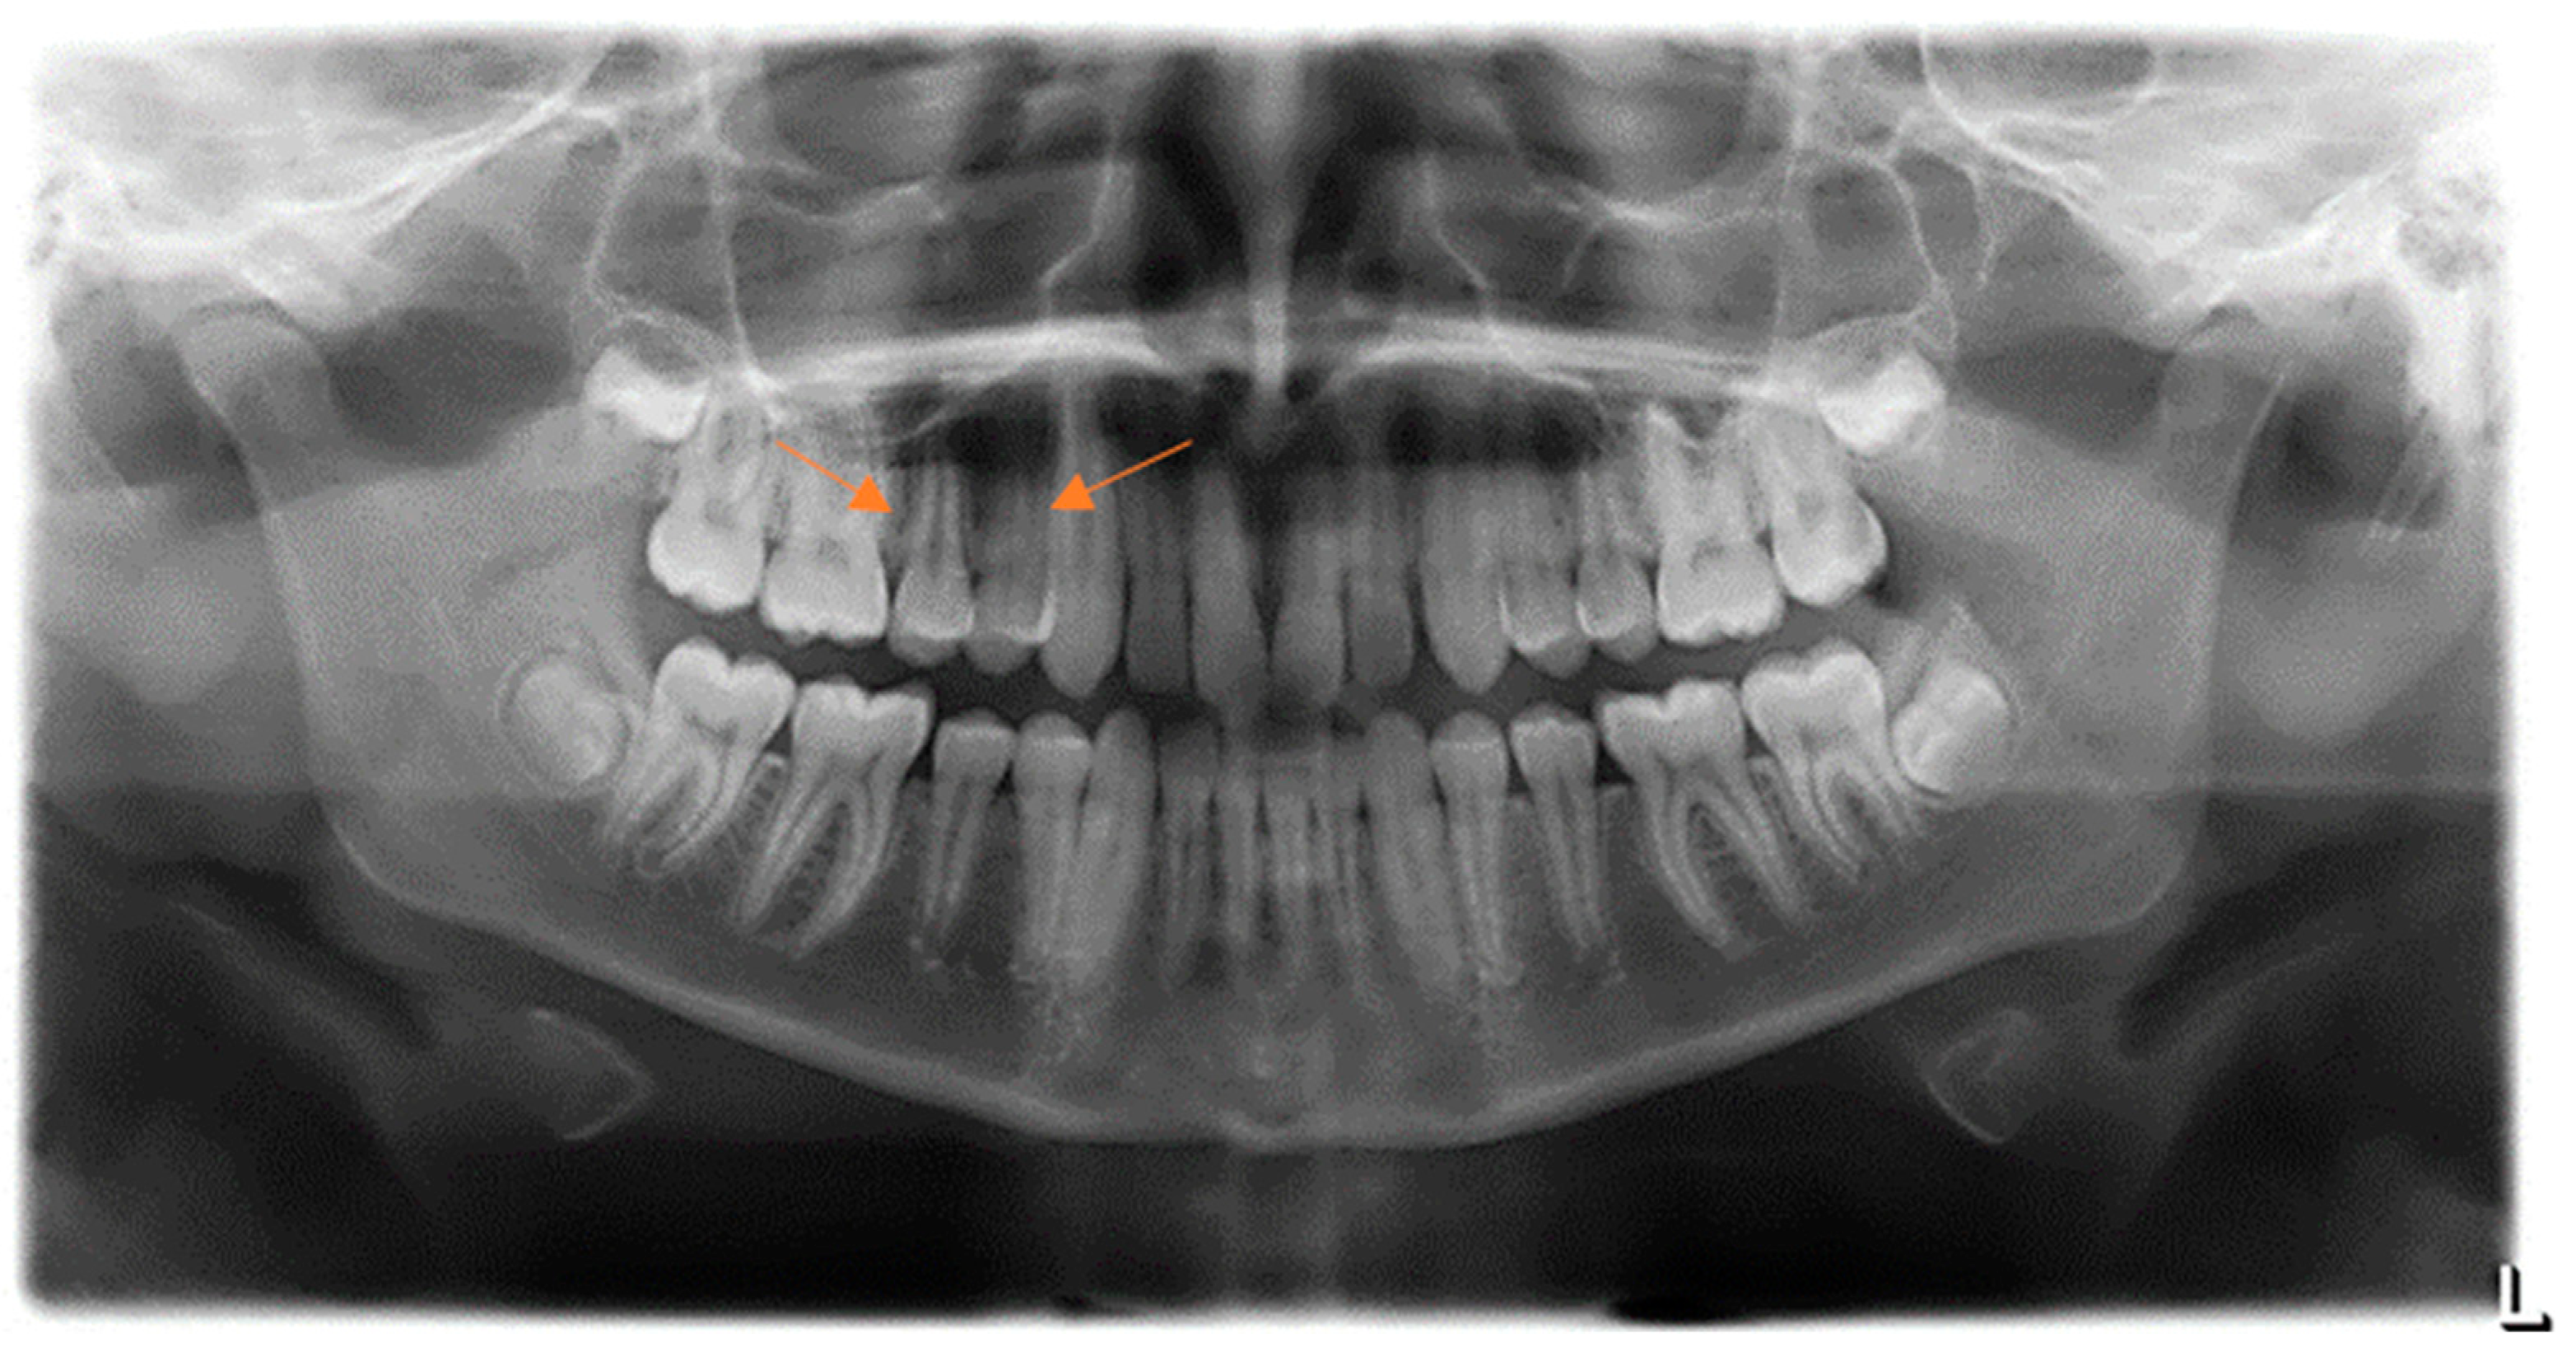

2. Case Presentation